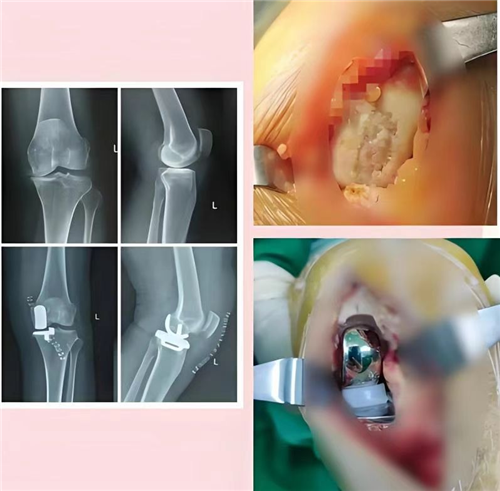

入院后,卢山主任团队对王奶奶的病情进行全面评估。检查发现,王奶奶在短距离行走、轻微下蹲时,膝关节功能严重受限,保守治疗已无法改善症状。鉴于其膝关节病变集中在内侧,团队一致认为,保膝手术——左膝关节单髁置换术是最佳治疗方案。

单髁置换术堪称“关节修复的精细手术”,它仅替换病变的膝关节内侧或外侧髁,最大程度保留健康关节组织与韧带,维持膝关节自然功能。相比全膝关节置换,单髁置换术创伤更小、恢复更快,患者能更快回归正常生活。在取得家属同意后,卢山手术团队顺利为王奶奶实施了手术。令人惊喜的是,术后第二天,王奶奶就能下地行走,这让她和家人倍感欣慰。

治疗膝骨关节炎,不能‘一换了之’,而要精准施策。”卢山主任介绍,目前膝骨关节炎的治疗强调个体化、精准化,单髁置换术就像“补牙”一样,用材料修复磨损软骨,让膝关节“延迟退休”。宿州市第一人民医院骨二关节科依托前沿理念,在术前评估、术中操作、术后康复等环节不断优化,让关节置换手术告别“漫长恢复期”,帮助患者快速无痛康复,大幅减少卧床时间与并发症,让关节功能早日恢复。